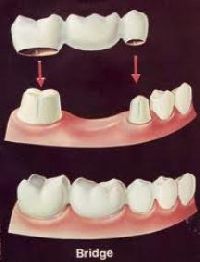

Fixed Crown

The metal ceramic crowns always have a slight metal hue whereas the all ceramic crowns are completely tooth colored and esthetic . Dental crowns, also known as "dental caps," "tooth crowns," or "tooth caps," are one of the most effective dental solutions that help cover over and encase the tooth on which they are cemented. Crowns may be used to protect a decayed tooth, strengthen teeth, restore a broken tooth or to replace a missing tooth. Dental crowns and bridges can be made of precious metal, gold, ceramic, porcelain-fused-to-metal metal free crowns. There is a wide range of crowns to choose from depending on the esthetic and functional requirement . Our office specializes in CAD CAM Alumina and Zirconia METAL FREE LAVA and PROCERA CROWNS for high precision and esthetic results. ALL CERAMIC EMPRESS CROWNS for unbeatable natural looking appearance. Gold DUCERA for that added strength and natural looking teeth. The type of crown we use depends on your specific dental needs.

Tooth extraction is the removal of a tooth from its socket in the bone. What It's Used For Sometimes, tooth damage is too extensive for the tooth to be repaired. This is the most common reason for extracting a tooth. Such a extraction site can easily be replaced with a new tooth with different options like an implant or a bridge